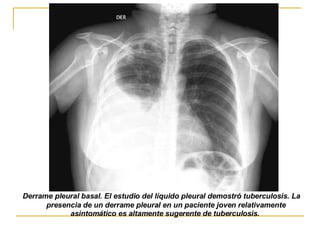

AFECTACIÓN PLEURAL 10% de los casos,  mas frecuentes entre los 15 a 30 años primaria.  El DP tiende  acumularse lentamente y sin dolor, la mayoría son unilateral El resultado final es la presencia de una restitución total del espacio pleural o simplemente del ángulo costofrenico

Derrame pleural basal. El estudio del líquido pleural demostró tuberculosis. La presencia de un derrame pleural en un paciente joven relativamente asintomático es altamente sugerente de tuberculosis.

AFECTACIÓN PLEURAL 10%de los casos, mas frecuentes entre los 15 a 30 años primaria. El DP tiende acumularse lentamente y sin dolor, la mayoría son unilateral El resultado final es la presencia de una restitución total del espacio pleural o simplemente del ángulo costofrenico

Derrame pleural basal.El estudio del líquido pleural demostró tuberculosis. La presencia de un derrame pleural en un paciente joven relativamente asintomático es altamente sugerente de tuberculosis.